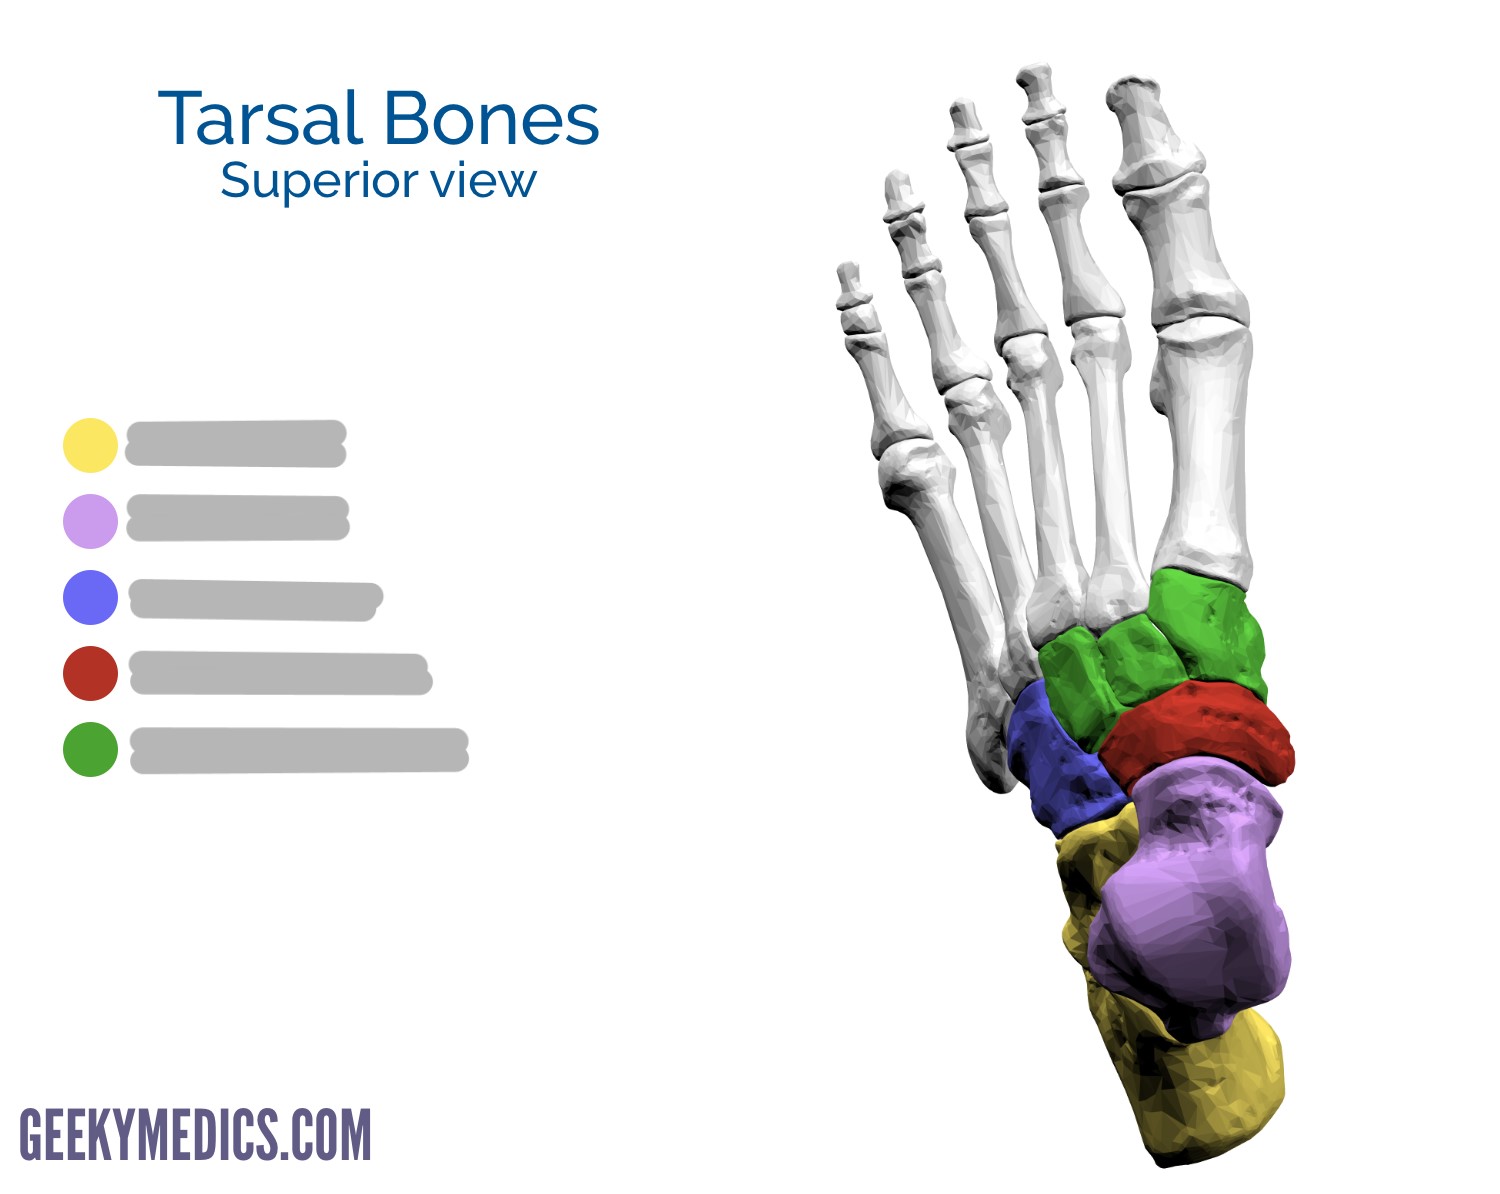

tarsals: 7

Explain the size and location of the 3 cuneiforms

1st: medial (largest)

2nd: intermediate (smallest)

3rd: lateral

The navicular is located on the ___ side of the foot and articulates distally with ___

medial; the cuneiforms

The cuboid is located on the ___ side of the foot and articulates distally with ___

lateral; MT 4 and 5